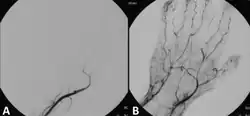

A Doppler evaluation is often the first imaging choice to diagnose ALI because it is inexpensive, accessible, non-invasive, and can be done in a short amount of time.[2] It is used to show the extent and severity of the ischaemia by showing flow in smaller arteries. An occlusion of the artery would be seen by decreased or absent flow distal to the occlusion. Doppler ultrasound can even distinguish between embolic and thrombotic plaque. The former would show a delineated, round thrombus, whereas the latter would show narrowed arterial lumen with atherosclerotic plaque.[2]

Although Doppler ultrasounds provide excellent information, there may be difficulty in evaluating aortic or iliac arteries in patients who are obese or have significant gas.[2] Other diagnostical tools are duplex ultrasonography, computed tomography angiography (CTA), and magnetic resonance angiography (MRA). The CTA and MRA provide higher-resolution images used in planning revascularization, but they may only be used in patients without a threatened limb due to time constraints. CTA uses radiation and may not pick up on vessels for revascularization that are distal to the occlusion, but it is much quicker than MRA.[1] In treating acute limb ischaemia, timing is everything.[18]

Endovascular intervention